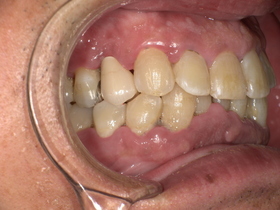

症例結果|Before / After

After

- 自然な白さ

- 違和感ゼロ

- 美しく機能的

👉 見た目も機能も大きく改善

治療詳細

- 年齢:50代男性

- 期間:約2週間(2回)

- 費用:セラミックジルコニア冠198,000円(税込)

土台 44,000円(税込)